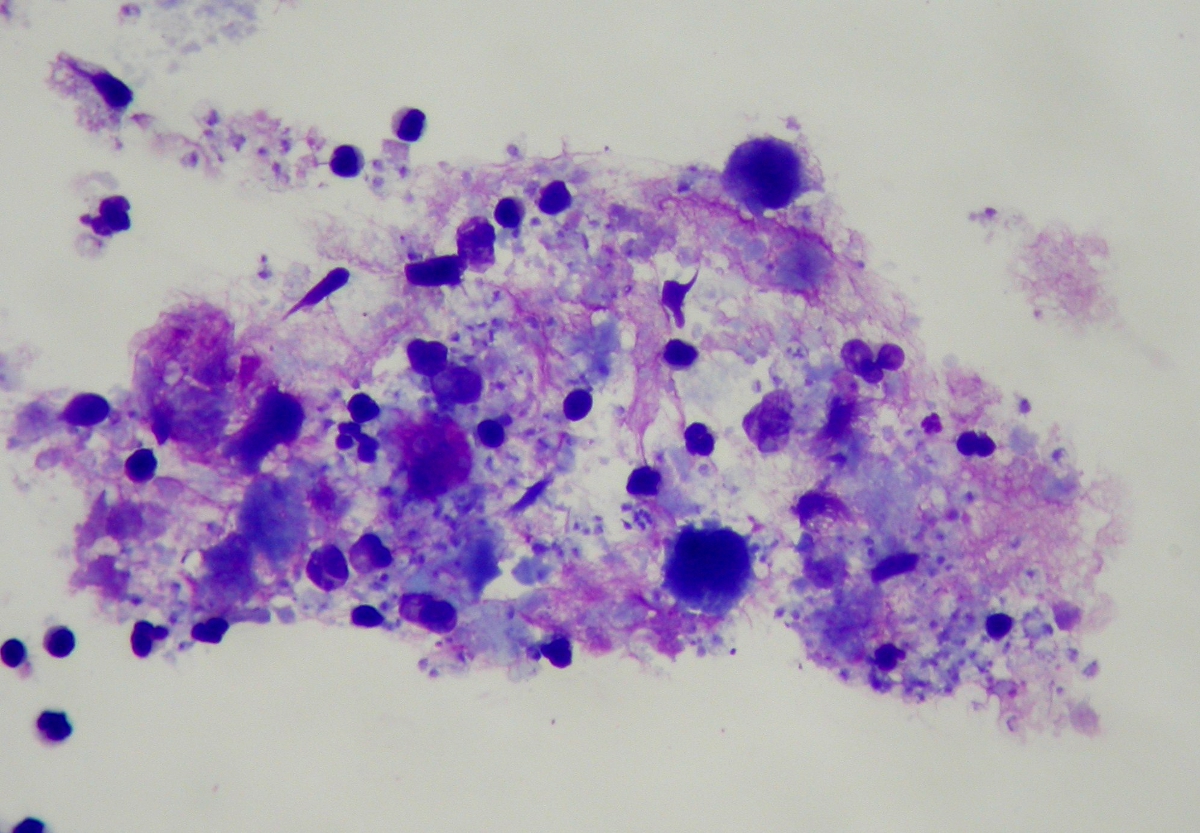

Фотографии бактерий, вызывающих бактериальные пневмонии у животных

Раздел: Другие животные